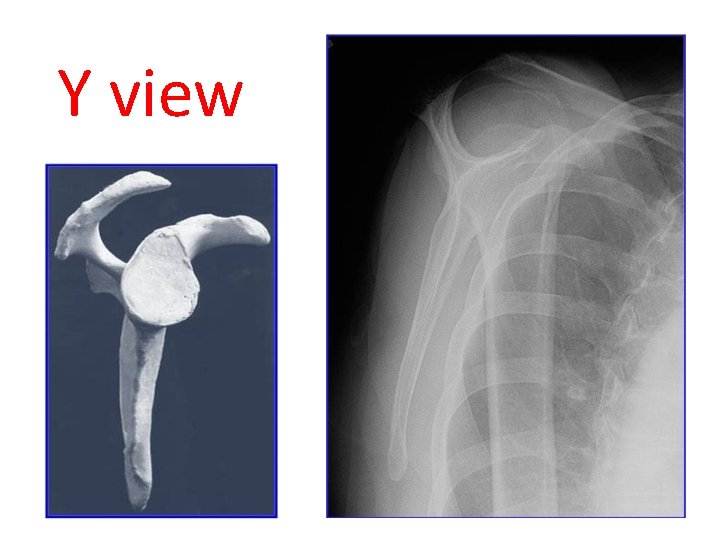

Y view

Y view acromion Humeral head spine coraocid scapula humors shaft